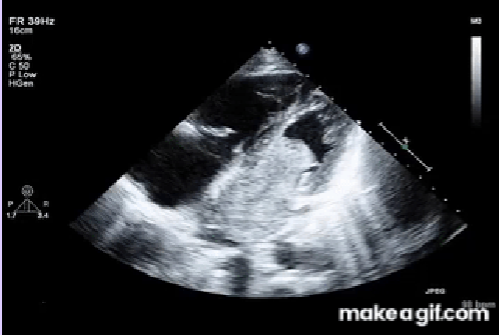

LV thrombus

Most common form of intracardiac thrombus due to impaired LV function.

Rarely occur in patients with preserved LV function.

Commonly found in the apex.

High risk for thromboembolic events, particularly stroke.

<p>Most common form of intracardiac thrombus due to impaired LV function.</p><p>Rarely occur in patients with preserved LV function.</p><p>Commonly found in the apex.</p><p>High risk for thromboembolic events, particularly stroke.</p>